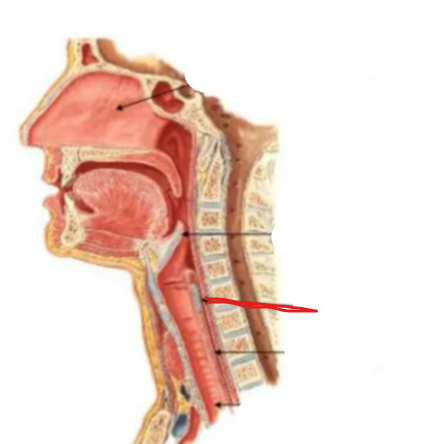

What structure is this?

Thyroid Cartilage

What structure is this?

Cricothyroid Ligament

Cricoid Cartilage

What structure is this?

Epiglottis

What structure is this?

Trachea

What structure is this?

Larynx

What are the three laryngeal cartilages?

epiglottis, cricoid and thyroid cartilage